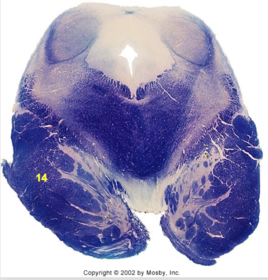

| Longitudinal pontine fibers (corticospinal tract) | |

| Transverse pontine fibers (dark fibers) | |

| Pontine nuclei (pale) | |

| Central tegmental tract | |

| ALS | |

| Medial longitudinal fasciculus | |

| Middle cerebellar peduncle | |

| Superior cerebellar peduncle | |

| Anterior spinocerebellar tract | |

| Principle nucleus of V | |

| Mesencephalic V tract | |

| Trigeminal root fibers | |

| Motor nucleus of V | |

| Cerebellar vermis | |

| Lateral lemniscus | |

| Medial lemniscus | |

| Ventral trigeminothalamic tract | |

| Longitudinal pontine fibers (c-spinal, c-bulbar, c-pontine fibers) | |

| Transverse pontine fibers (dark) | |